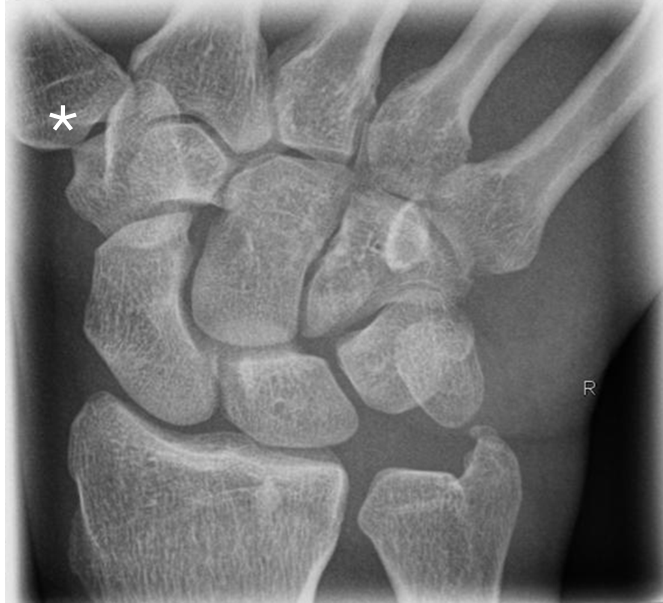

2.126 Welcher Gelenktyp gehört das mit einem Stern markierte Gelenk in der folgenden Abbildung?

Antwortmöglichkeiten

• (A) Kugelgelenk

• (B) Radgelenk

• (C) Sattelgelenk

• (D) Zylindergelenk

• (E) Eigelenk